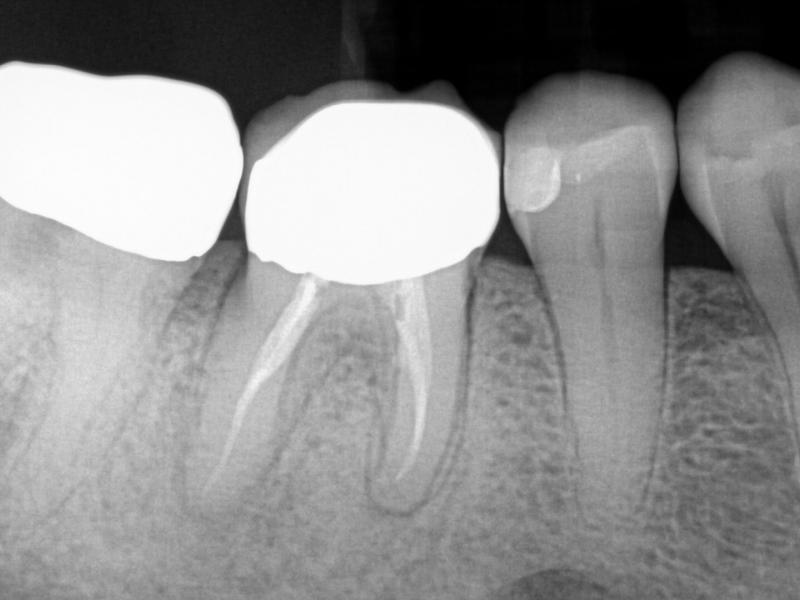

Post-Op